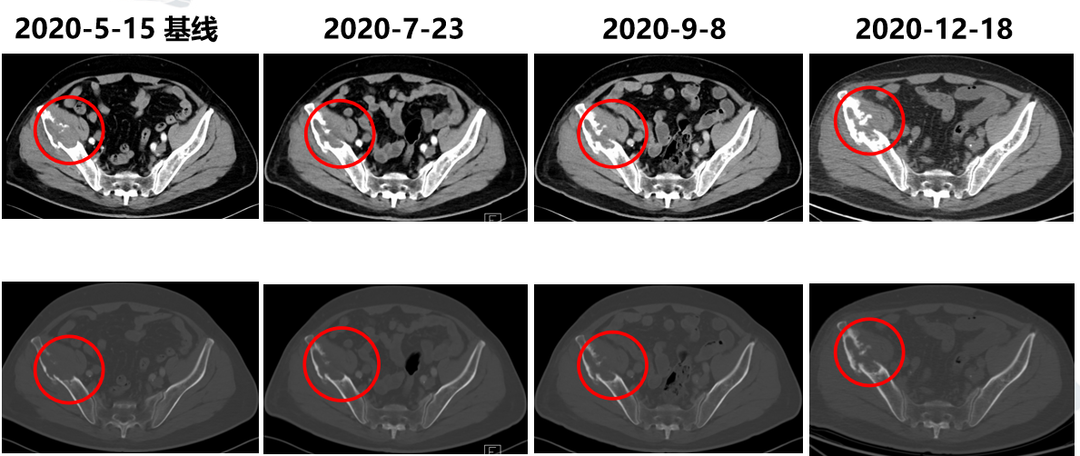

患者自2020年5月22日起开始接受替雷利珠单抗联合吉西他滨方案治疗,期间我们针对右髂骨和肝转移灶给予了放疗。6个周期联合治疗后,调整为替雷利珠单抗单药维持治疗。10个周期后疗效评价达到部分缓解(PR),至今OS已超过1年。尽管患者有多年的高血压病和2型糖尿病史,整个治疗过程仍能良好耐受,未出现严重不良反应,也未发生免疫相关不良事件。虽然结局可喜,但期间3次出现假性进展,为肿瘤治疗的决策带来了很大挑战。

患者治疗前后骨转移灶影像对比:10周期后(2020年12月18日)疗效评价达到PR